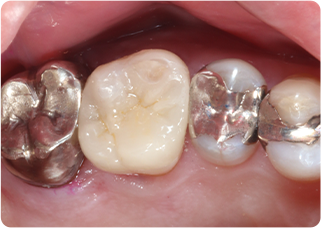

セラミックアンレー症例④

術前

インレー除去

ラバーダム防湿

シリコン印象

技工物

術後

| 主訴 | 右上奥歯の銀歯に食べ物が挟まる |

|---|---|

| 治療期間/回数 | 2週間、2回 |

| 価格(税込) | 77,000円(税込) |

| リスク・副作用 | セラミックの破損、一時的な知覚過敏が生じる場合がある |

| ポイント | 銀歯の詰め物の中がむし歯になっていたため、う蝕検知液を使用し選択的にむし歯のみを除去。またセラミック装着時にラバーダム防湿を行うことで、詰め物の接着効果を最大限発揮できるようにした。 |